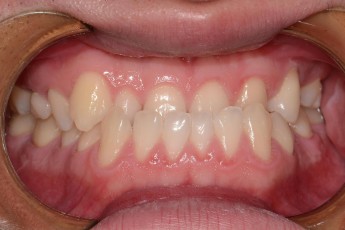

Before

After